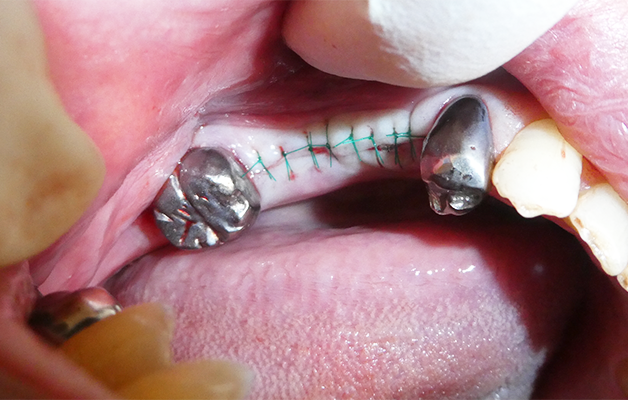

埋入時の縫合

出来るだけ低侵襲の手術を心がけています。

切開線も必要最小限に設定し、術後の痛み・腫れを最小限に抑えます。